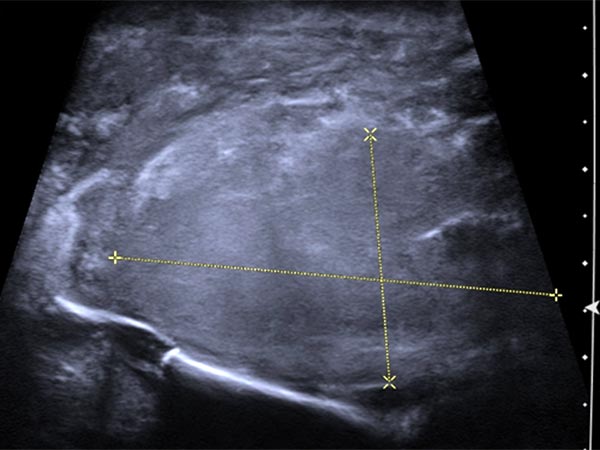

Sonographically, the main subcutaneous extent of the tumor is seen in the depth of the buttock on the right side. The tumor is echogenic, but overall very inhomogeneous and extends to the pelvic bone.

In color-coded duplex sonography the tumor shows marked perfusion. The suspicion of a vascular tumor is thus substantiated.